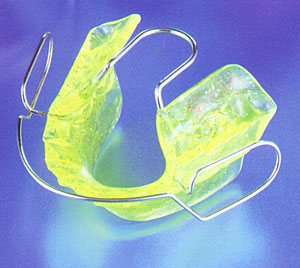

mit Bionatoren (nach Prof. Dr. W. Balters) zur Normalisierung der Zungenlage und Funktion durch Stimulation der Zunge durch den Zungenbügel, sowie zur Wachstums- förderung des Unterkiefers, zur Entspannung der Kiefermuskulatur, zur Normalisierung der Durchblutung und Förderung des Lippenschlusses |

Bionator *